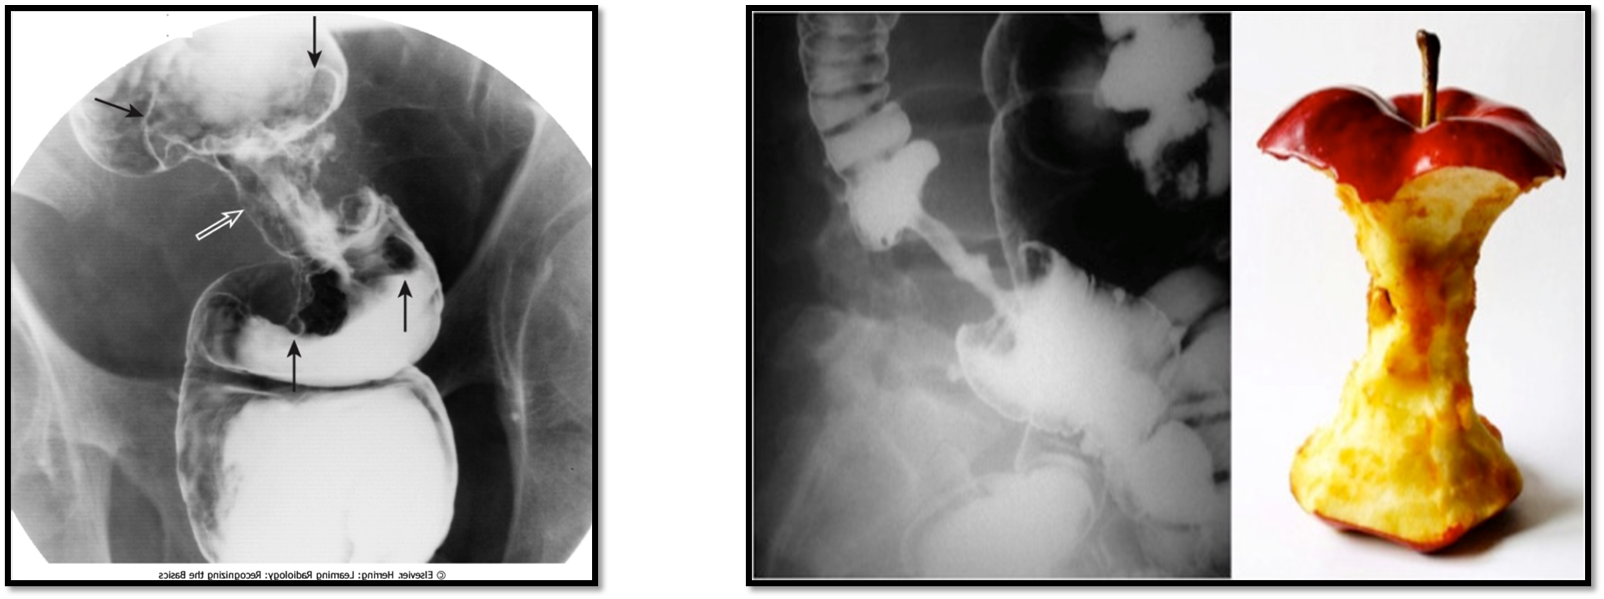

Colorectal Cancer

_____ is the third leading cause of cancer death in the United States.

Peak age incidence is 50 to 70 years old.

It is twice as common in men.

About half of colon carcinomas occur in the rectum and sigmoid.

Obstruction is a common finding

Predisposing factors:

Long-term ulcerative colitis (UD)

Familial polyposis (glandular polyps in the colon and rectum).

Radiological Appearance:

Apple core sign